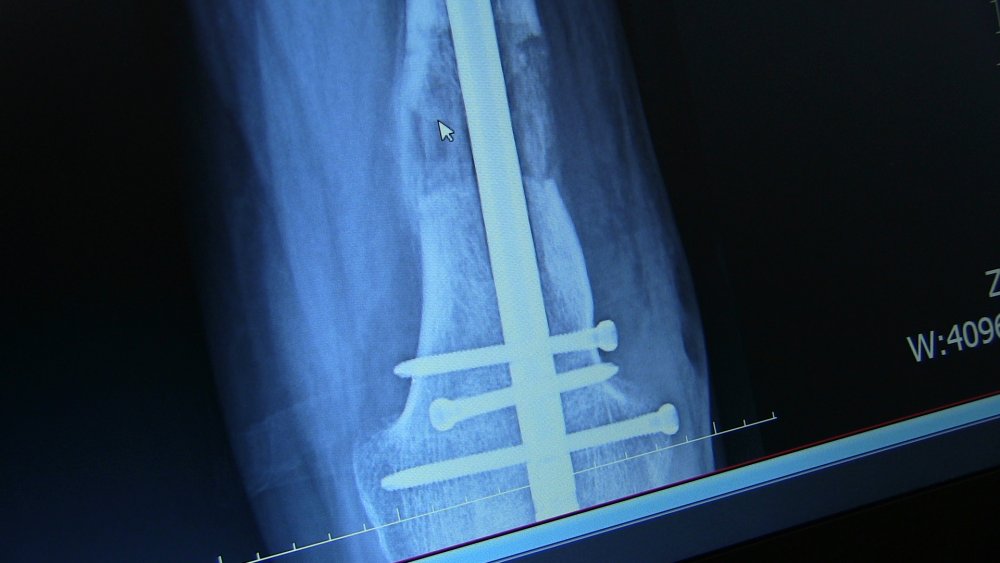

Platin ve çivilerle ayağındaki kısalık giderildi

Operasyonu gerçekleştiren Farabi Hastanesi Ortopedi ve Travmatoloji Uzmanı Prof. Dr. Mehmet Arazi ise hastanın kendilerine müracaat ettiğinde, sol bacağında ciddi bir kısalık, diz bölgesinde eğrilik ve ayağında fiziksel bozukluk olduğunu söyledi.

Hastanın yaşı ilerledikçe yürüme probleminin arttığını, sol ayağının sadece ayak parmaklarını yere basabildiğini dile getiren Arazi, "Hastamızın, ardışık ameliyatlarla bacağındaki kemikleri uzatabilme, dizindeki ve ayağındaki problemleri giderme kararı aldık. Yaptığımız ameliyatla ilk olarak bacağındaki şekil bozukluğunu düzelttik. Ardından tıbbi olarak kullandığımız çivi ve platinlerle dizin üstündeki ve dizin altındaki kemiği uzattık. Ardından topuk ve ayak bileğindeki bozukluk için de bir operasyon yaptık. Şu anda sağlığı iyi durumda." diye konuştu.